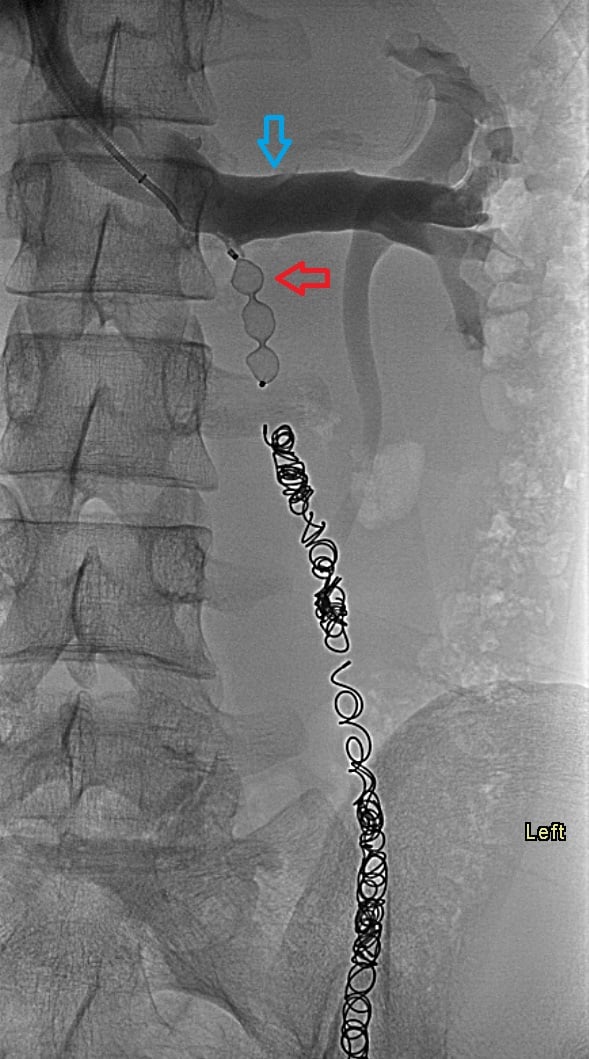

17-year-old male with a long history of left-sided varicoceles status post surgical ligation in 2015 presents with recurrence of symptoms, referred to us for left gonadal vein embolization.

Ultrasound demonstrates enlarged veins (>3 mm) adjacent to the testicle. Angiogram demonstrates reflux of contrast into the left gonadal vein to the level of the scrotum, indicating venous valvular incompetence. Coil embolization and sotradecol sclerotherapy of the left gonadal vein were performed, with an Amplatzer plug at the top of the vein. Repeat angiogram demonstrates no contrast opacification of the vein. Red arrows indicate the left gonadal vein and the blue arrows indicate the left renal vein.